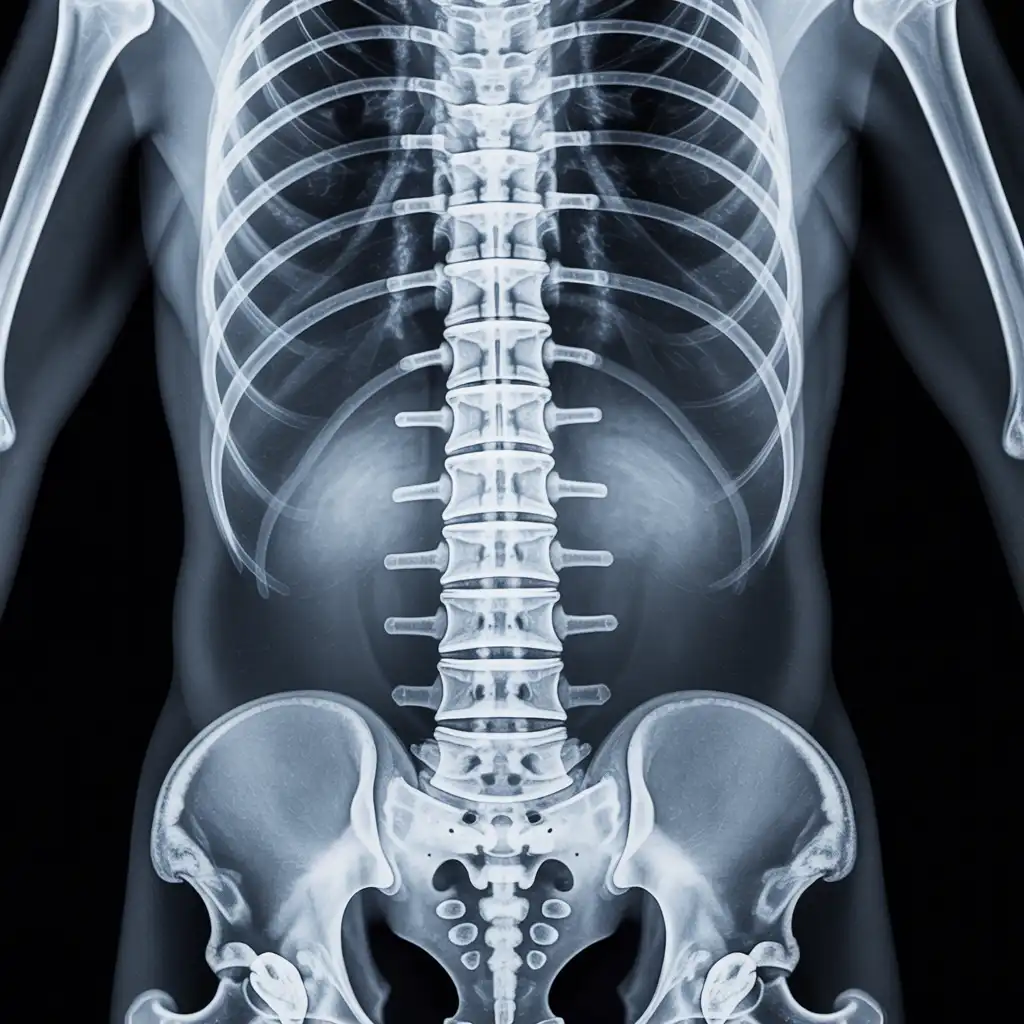

Una lastra a domicilio è una radiografia eseguita direttamente a casa del paziente, grazie all’intervento di un tecnico sanitario qualificato dotato di apparecchiatura digitale portatile.

L’esame viene effettuato sul posto, senza necessità di spostare la persona dal letto o dalla poltrona, e garantisce una qualità diagnostica paragonabile a quella di un reparto ospedaliero.

Una volta acquisite, le immagini vengono trasmesse al medico radiologo, che le analizza e redige il referto in tempi brevi.

Ricevi tutto comodamente in formato digitale: un servizio pratico, sicuro e pensato per chi ha difficoltà negli spostamenti o necessita di un percorso sanitario più semplice e immediato.